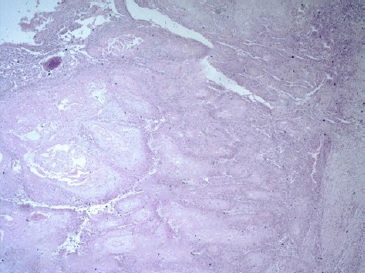

Histopathological analysis of the resected specimen revealed fragments of oral mucosa lined by hyperparakeratinized stratified squamous epithelium, showing an area of central depression filled with keratin, numerous corneal pearls, pseudo-epitheliomatous hyperplasia, and areas of epithelial dysplasia, confirming the diagnosis of keratoacanthoma (Figures 4 and 5).

Figure 4 Histopathological section showing intense epithelial proliferation with marked dyskeratosis (keratin production by means of corneal pearls and keratinization of individual cells) (HE, 10X).

Figure 5 Histopathological section showing pseudoepitheliomatous hyperplasia, excessive production of keratin, and the presence of corneal pearls (HE, 20x).